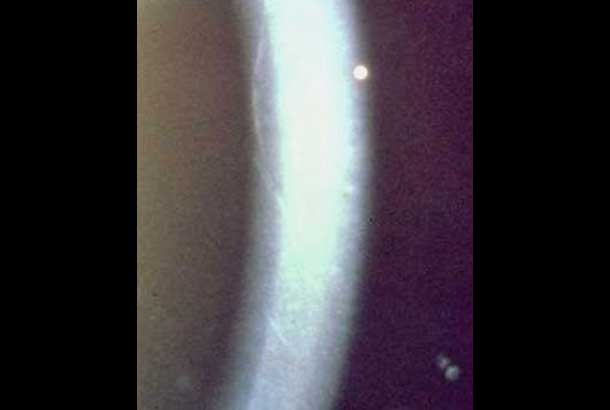

"id": 74,

"url": "https://cclm.media-doc.io/conditions/74/?format=api",

"name": "H. Sclerotic Scatter",

"category": "Biomicroscope",

"detail": "<h2>&nbsp;</h2>\n\n<h2>Overview</h2>\n\n<ul>\n\t<li>The technique uses&nbsp;total internal reflection of the cornea</li>\n\t<li>It allows the cornea to be assessed for the presence of edema or corneal opacities</li>\n\t<li>The illumination and observation systems are uncoupled</li>\n</ul>\n\n<p>&nbsp;</p>\n\n<h2>Set Up</h2>\n\n<ul>\n\t<li>The illumination system is uncoupled from the observation system</li>\n\t<li>Low magnification is used</li>\n\t<li>A moderate width light beam is directed at the limbus</li>\n\t<li>The observation system is focussed on the central cornea</li>\n\t<li>When total internal reflection is acheived, the whole limbus is illuminated</li>\n</ul>\n\n<p>&nbsp;</p>\n\n<h2>Useful when assessing</h2>\n\n<ul>\n\t<li><a href=\"/condition/14\">Corneal Edema - Stromal</a></li>\n\t<li><a href=\"/condition/27\">Corneal Opacities</a></li>\n</ul>\n\n<p>&nbsp;</p>\n\n<p>&nbsp;</p>",